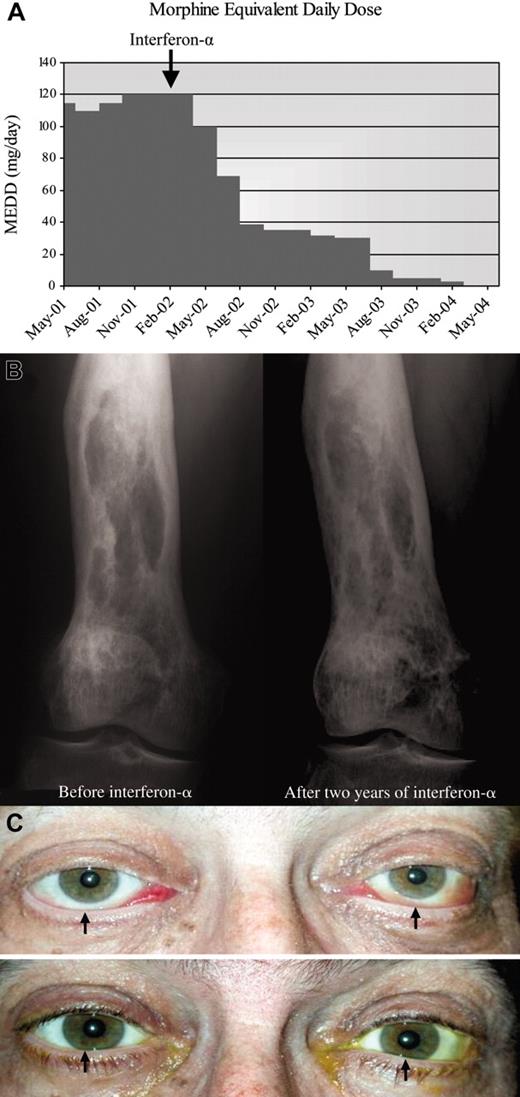

A 58-year-old man was evaluated for ongoing leg pain, treated diabetes insipidus, and panhypopituitarism. The long bone radiographs of his legs showed bilateral osteosclerosis of the diaphyses and metaphyses sparing the epiphyses of the femur and tibia. A right femur bone biopsy revealed infiltration with diffuse large foamy histiocytes, Touton-like giant cells and lymphocytic aggregates and fibrosis diagnostic of Erdheim-Chester disease. 99mTc-MDP bone scan identified multiple long bone lesions as well as T11 thoracic and L3 lumbar vertebral lesions. Unfortunately, neither radiotherapy to his spine and knees nor strontium-90 radionuclide nor high-dose prednisone halted the ongoing progression of his disabling pain syndrome requiring high-dose opioids. Interferon-α, 3 × 106 units subcutaneous 3 times per week, later decreased to 1 × 106 units because of significant fatigue was very well tolerated and allowed tapering down his opioids within 3 months (Figure 2A). After 2.5 years of interferon-α maintenance therapy, he is pain free and off analgesics, and the follow-up tests show significant improvement of the bone radiographs (Figure 2B).

Response to interferon-α in patients 2 and 3. (A) Morphine equivalent daily dose (MEDD; mg/d) needed to manage pain before and after interferon-α therapy. Patient required 120 mg/d opioids before starting interferon-α. After 2 years, he no longer needs opioids. (B) Bone radiograph of the right femur reveals mixed osteosclerotic and osteolytic lesions before treatment. Ongoing improvement is seen after 2 years of treatment with interferon-α. (C) (Top) Bilateral exophthalmos with chemosis, engorged conjunctival vessels, and inferior scleral show (arrows) at presentation. Loss of eyelashes because of recent chemotherapy is noted. (Bottom) Exophthalmos, chemosis, and inferior scleral show (arrows) resolved after 2 years of interferon-α. Eyelashes have grown back.